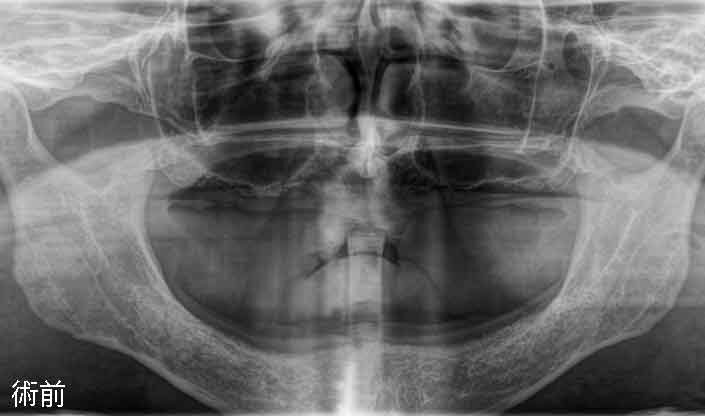

手術日当日 術前

allon4 手術

この患者さんの術前のパノラマX線画像ですが、昔ボクシングをされていたそうで上顎の歯をほぼ全てなくしていました。どこの歯科医院にいっても「上顎の骨がないから入れ歯しか施術できない」と言われたそうです。まだ若かったこともあり、入れ歯自体を受け入れることができなかったそうです。手術前に麻酔専門の医師が静脈鎮静麻酔を行います。この麻酔法により緊張感や恐怖心はなくなり、鎮静剤の点滴を行いながらリラックスした状態で手術が受けられます。しかも、入院の必要はなく、処置が終了すればその日に帰宅できます。